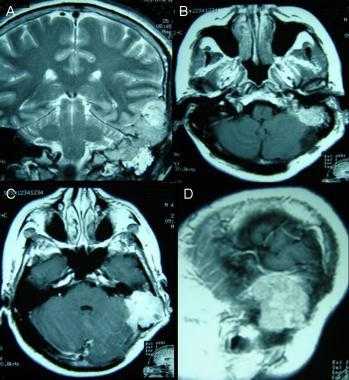

А: на Т1-взвешенном МР-изображении отмечается солидное образование, характеризующееся изоинтенсивностью по отношению к твердой мозговой оболочке, инвазией в кость и сдавлением теменных зон коры.

В: На Т1-взвешенном МР-изображении с контрастным усилением видна частично контрастируемая опухоль.

С: На корональном Т2-взвешенном изображении видно изоинтенсивное образование, что соответствует плотной ткани. Такая картина характерна для фибробластных менингиом.

D : На Т1-взвешенном МР-изображении с контрастным усилением визуализируется гиперинтенсивное образование внутри мозгового вещества кости.